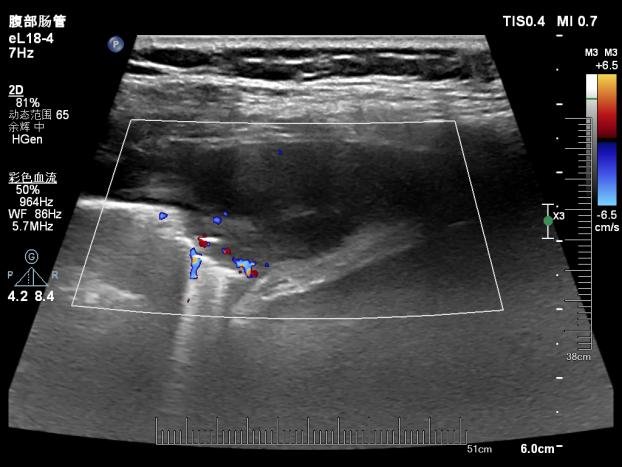

线阵探头显示结节内可见血流信号

超声医学科主任潘国栋与主治医师刘金昊依据超声显示的病变范围,细致规划了穿刺点、进针路线及深度,避开了肋间动脉、神经及病变侧方的肺组织。全程在超声的实时引导下,穿刺针精准到达病变部位,采集了2条病变组织。

经超声引导下避开血管、实时显示穿刺针从进入胸膜结节到击发穿刺针的全过程